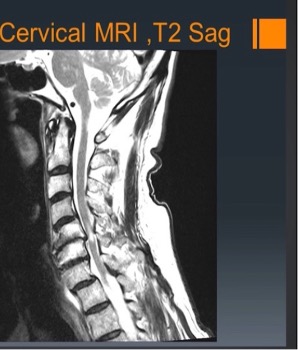

• Nerve compression: disc herniation or bone spurs can progress on the nerves coming out of your spinal cord.

• X-rays, CT scan, MRI or EMG and helps to make the diagnosis.